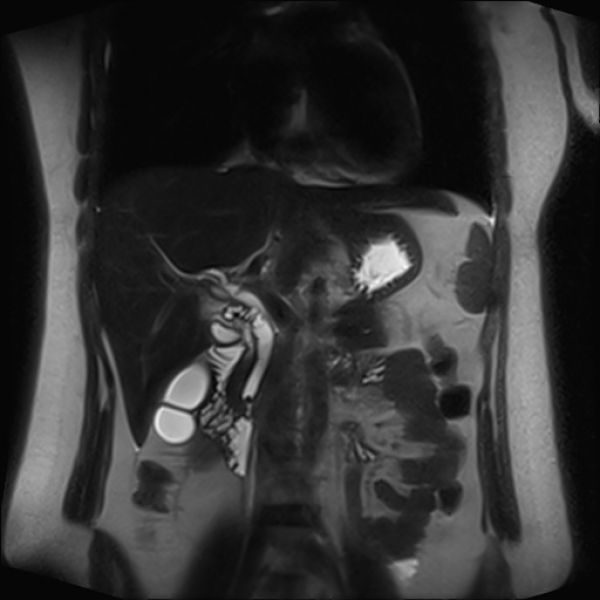

25岁的女患者龚某,因“反复上腹痛6月,再发加重4天,黄疸3天”入院。入院后完善急诊肝功能:TBIL65.3umol/L,DBIL39.5umol/L,ALT368U/L,AST125U/L;磁共振检查:“胆囊结石、胆总管胰腺段末端胆道梗阻”。根据术前相关检查,患者诊断十分明确,那么该患者治疗方案如何选择呢?

术前放置鼻胆管引流

三镜联合是目前新兴微创术式即腹腔镜、纤维胆道镜及电子十二指肠镜联合下治疗胆总管结石,首先通过电子十二指肠镜放置鼻胆管胆道减压,然后利用腹腔镜及纤维胆道镜实施胆囊切除及胆总管切开取石,并实现胆总管一期缝合,促进患者加速康复,明显提升患者生活质量的联合微创新术式。